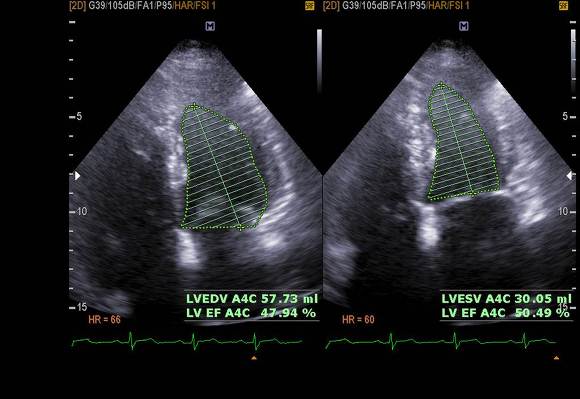

pic 6. EF 50.5%

history - HTN

pic 5. LA enlargement (almost 70ml) also RA enlarged